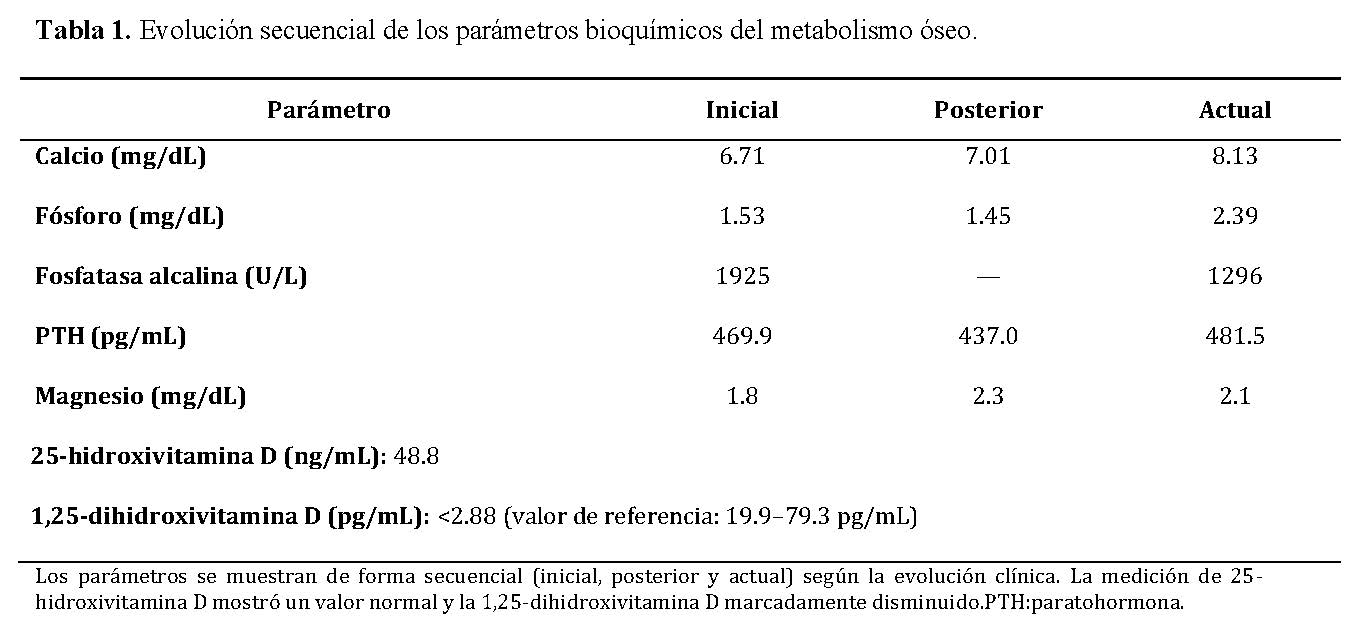

Los estudios bioquímicos revelaron alteraciones severas del metabolismo mineral, con hipocalcemia persistente, hiperparatiroidismo secundario, elevación marcada de fosfatasa alcalina., niveles normales de 25-hidroxivitamina D y una marcada disminución de la 1,25-dihidroxivitamina D.

La combinación de un patrón de raquitismo calcipénico, caracterizado por hipocalcemia e hipofosfatemia, fosfatasa alcalina severamente elevada e hiperparatiroidismo secundario, junto con niveles normales de 25-hidroxivitamina D y una marcada disminución de la 1,25-dihidroxivitamina D, es altamente sugestiva de un defecto en la activación de la vitamina D.

La evolución secuencial de los parámetros bioquímicos se resume en la Tabla 1, donde se evidencia hipocalcemia persistente, hiperparatiroidismo secundario marcado y descenso progresivo de la fosfatasa alcalina tras el inicio del tratamiento.